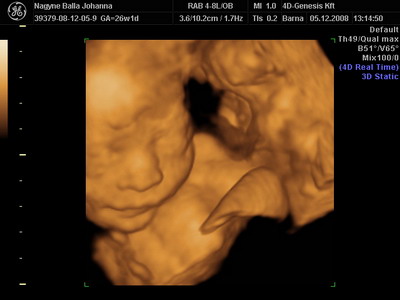

Csilla, az uh-s hölgy volt nagyon jó fej. Kérdezte, tudjuk-e ki lakik a pociban, mondtuk, kisfiú. Erre azt mondta, nézzünk rá. Kereste, Lukács mutatta, kis fütyi így, kis fütyi úgy, aztán fordult a kép, és Csilla nagy nevetve, nem is kicsi annyira ez a kis fütyi!

Akkor mérte le!